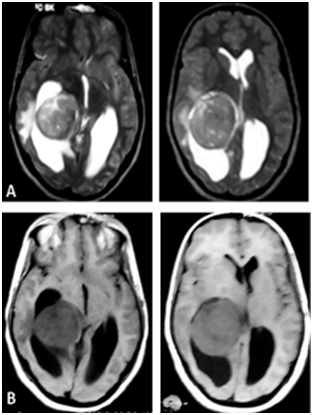

A 17years old female, presented with increasing intracranial pressure syndrome, severe headache, vomiting, and papillary oedema grade1. The patient was without any sensory or motor deficit. The CT and MRI shows a huge intraventricular lesion located in the occipital Horne of the right lateral ventricle (Figure 1). The patient underwent a ventricular shunting, and the tumor was excised in a second time. The removal was complete using a temporo parietal approach, and the post operative status was stable, with improvement of the headache. The histological exam indicates a fibroblastic meningioma (Figure 2).

Figure 1 Axial (A) T2-weighted and (B) T1-weighted MRIs showing a right lateral intraventricular meningioma.Notice the regular aspect of the lesion.